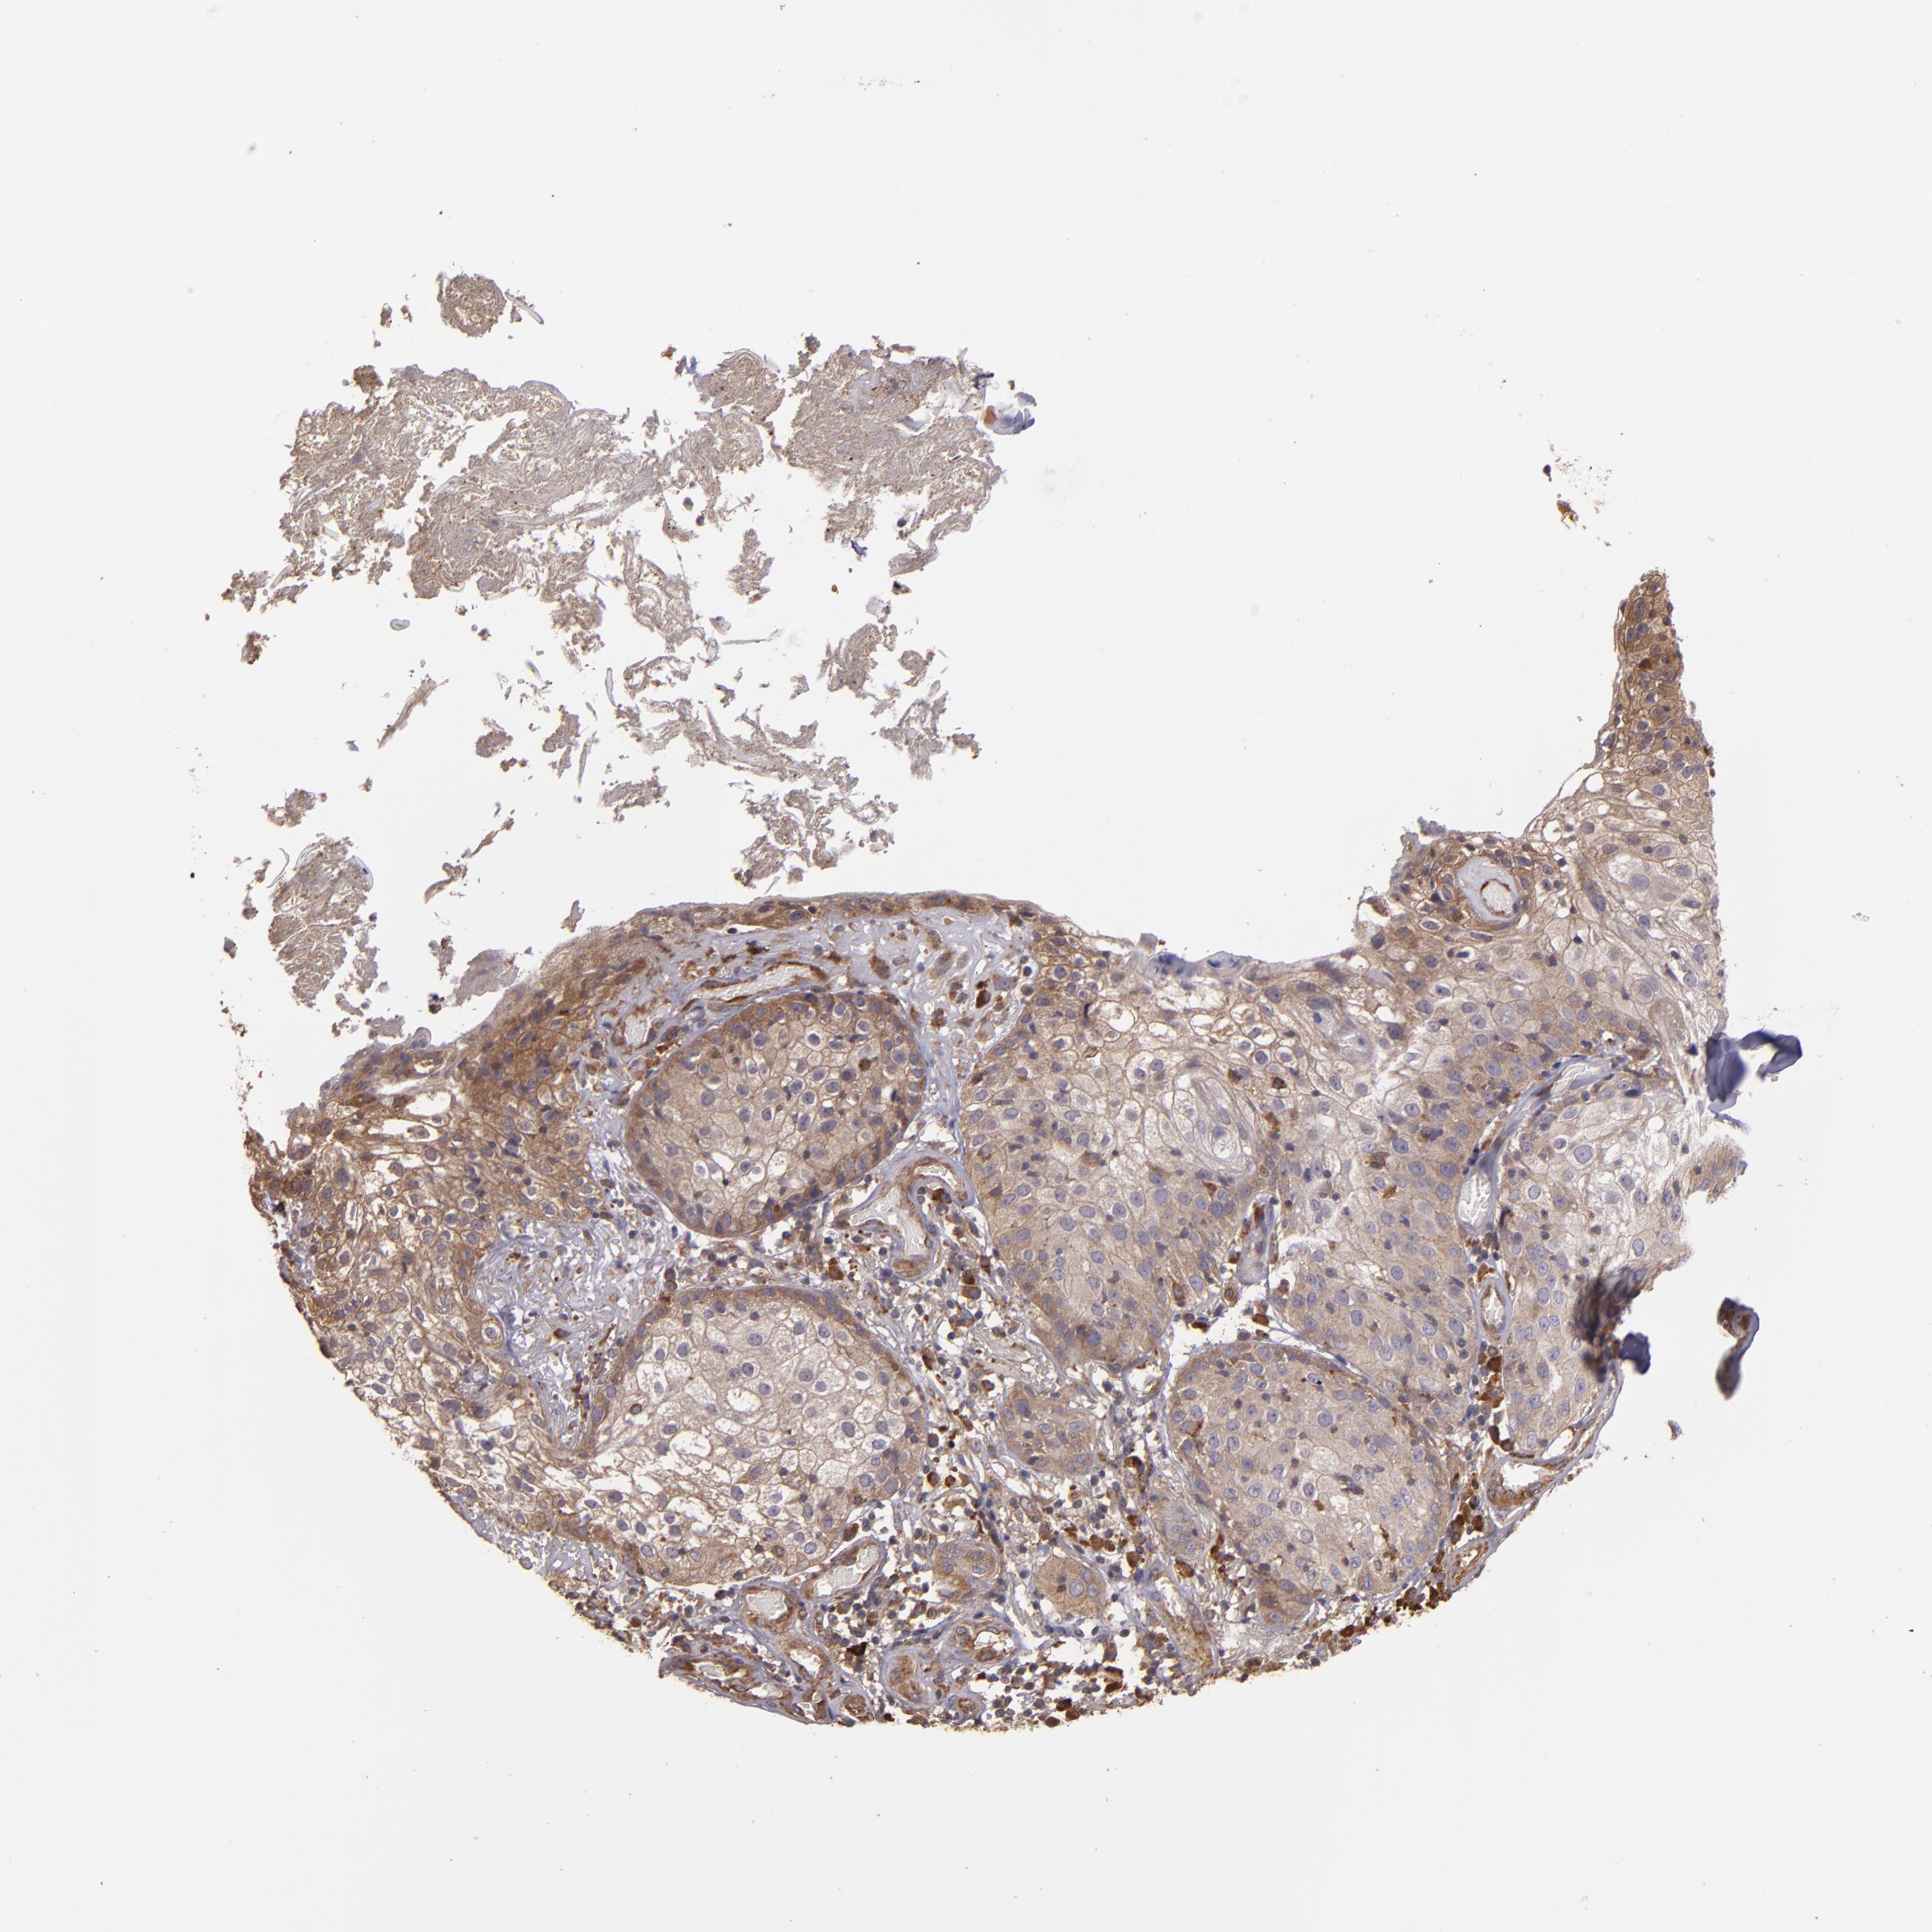

SKIN CANCER - Protein expressioni

A mouse-over function shows sample information and annotation data. Click on an image to view it in a full screen mode. Samples can be filtered based on level of antibody staining by selecting one or several of the following categories: high, medium, low and not detected. The assay and annotation is described here.

Each image is clickable and will lead to virtual microscopy that enables deeper exploration of all samples and also displays staining intensity scores, fraction scores and subcellular localization as well as patient and tissue information for each sample.

Antibody HPA001490

Squamous cell carcinoma, NOS